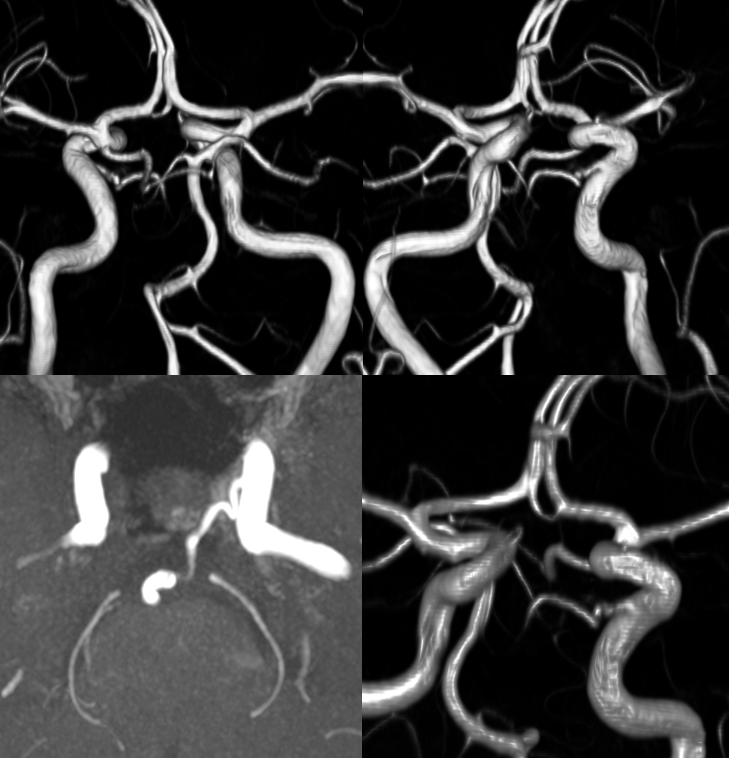

Spectrum — those “classic” cases of huge trigeminals and small PCOMs and small verts are just part of the spectrum. Just like PCOMs range from tiny to fetal, so do trigeminals. As mentioned above, everyone has a tiny trigeminal on the surface of the trigeminal nerve. Here is an infundibulum of small trigeminal artery seen from both ICA and vert